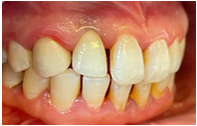

2 months after sealing (Figures 23–27). In implantology, connective tissue grafting is indicated at all stages of implant therapy to guarantee an optimal aesthetic result. Connective tissue tunnel grafts has been chosen. After 2 months of surgery, we note a good aesthetic result and the satisfaction of the patient.

Figure 26 Clinical results after 10 days.

Figure 27 Clinical results after 2 months.